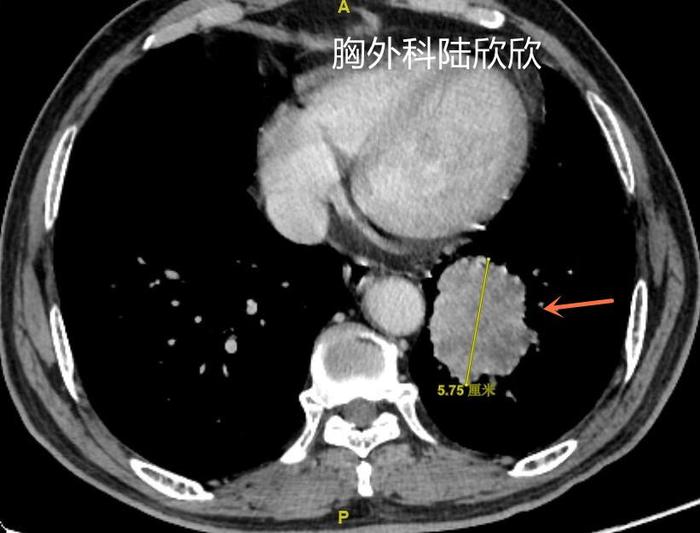

下面给大家看看一例最大径57毫米的左下叶肺癌的治疗经过。

上图,可见肿瘤较大,最大径57毫米。不是周围型肺癌,也不是中心型肺癌,介于两者之间,可以称为“中间型肺癌”。